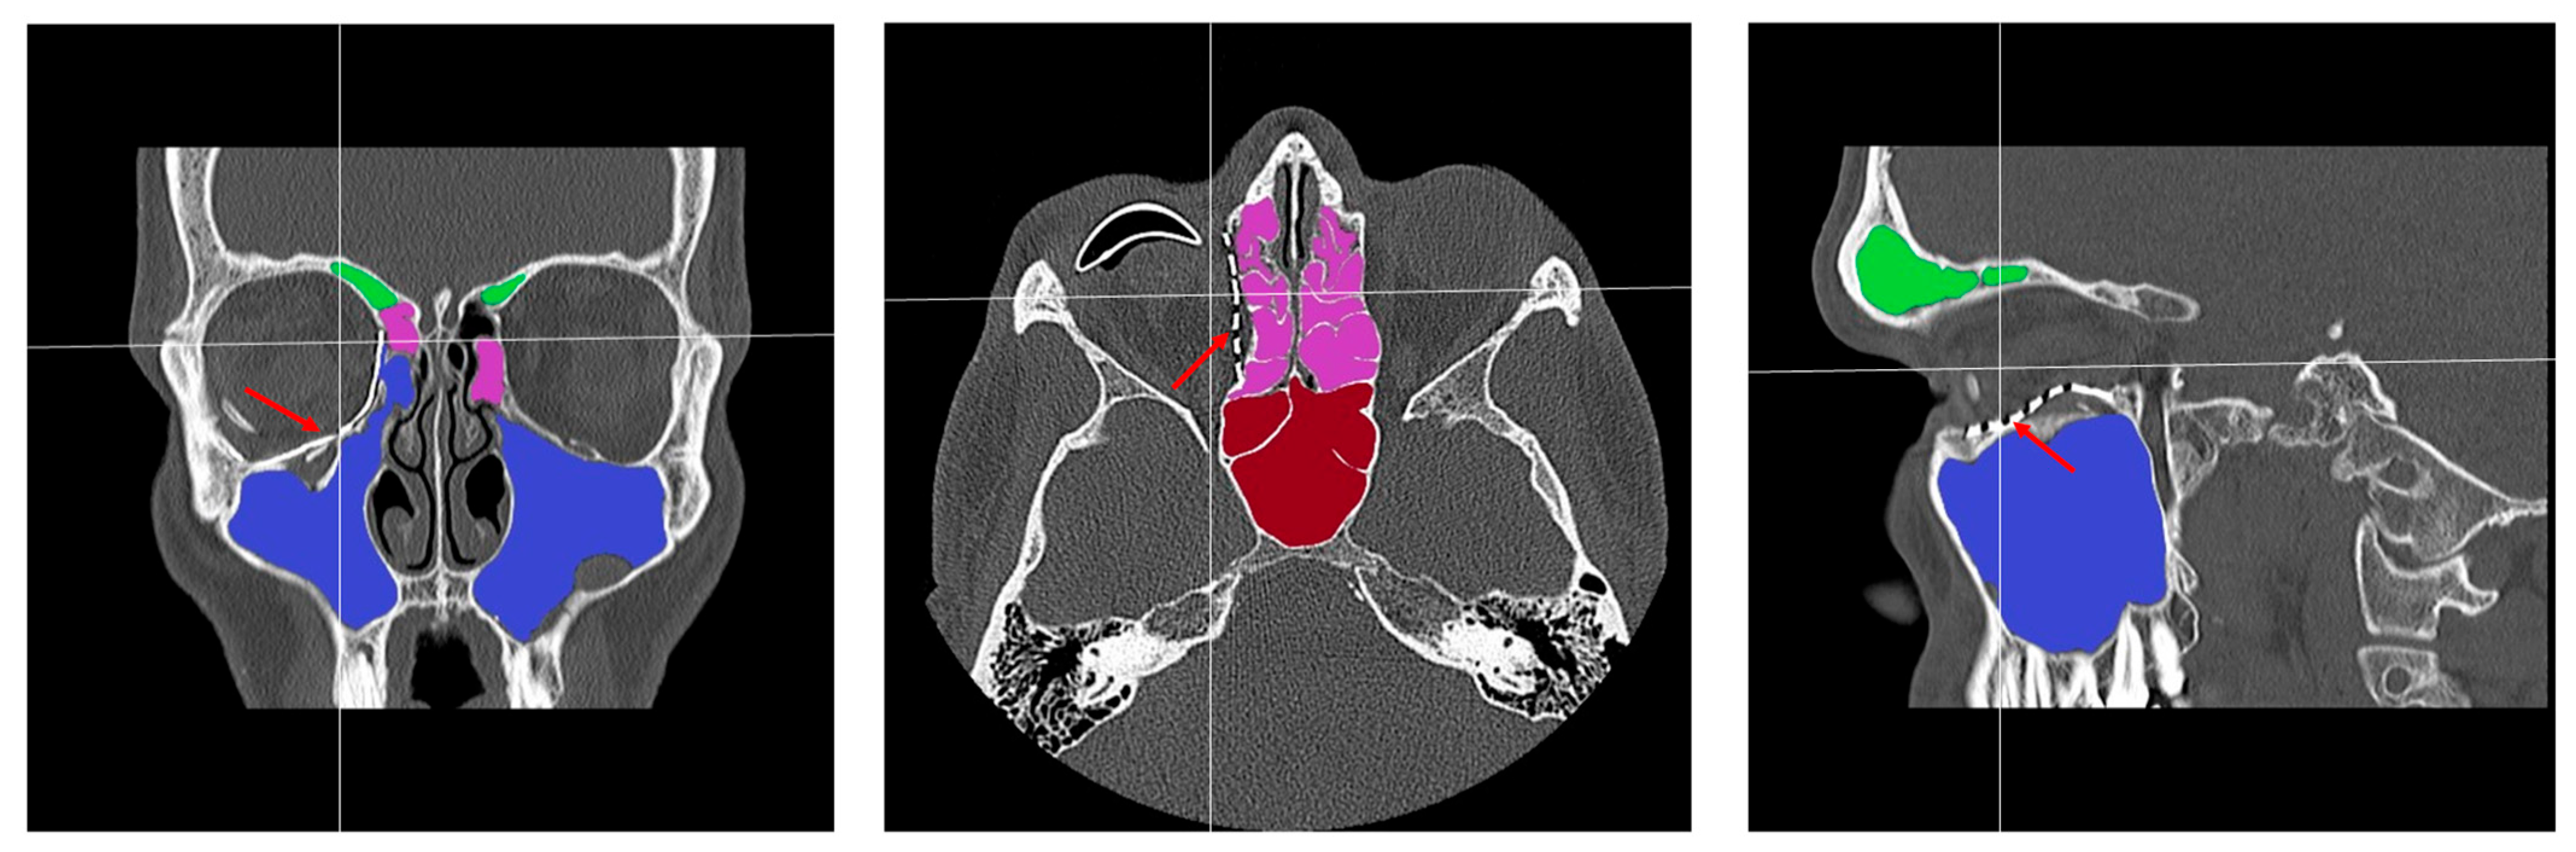

- Patent ostium of the maxillary sinus (coronal plane)

- Non-inflammatory PNSs (three planes)

- Exposure of the osteosynthesis screws (axial and sagittal planes)

- Exposure of the PSI to the maxillary sinus (coronal and sagittal planes)

- Remodeling of the fractured orbital walls and bone apposition at the PSI indicating osseointegration (three planes)

- Exposure of the fixation screws (infraorbital recess of the maxillary sinus) and limited exposure of the PSI (transition zone, ethmoid cells) without signs of mucosal swelling in these regions (n = 6 each)

- (Basal) mucosal swelling in the maxillary sinus indicative of chronic maxillary sinusitis, irrespective of the complexity of the primary injury (n = 4)